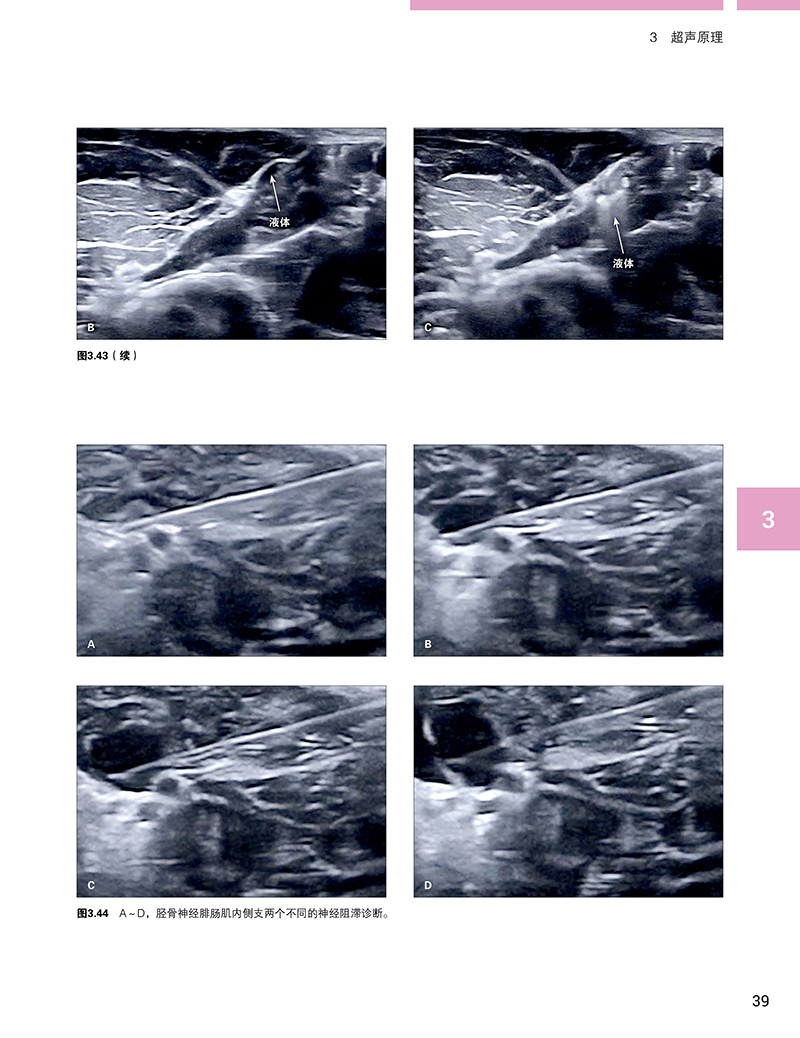

本书详尽介绍了超声技术及其在神经阻滞技术上的应用,以及相关的外周神经解剖。大量的超声图谱让读者熟悉如何在超声图像中确认这些神经及其分支。本书也对不同的神经阻滞技术(苯酚和冷冻神经阻滞)进行了详尽的临床病例报道。同时,还强调了利用利多卡因注射作为诊断性神经阻滞在肌痉挛治疗方面的价值,值得借鉴。